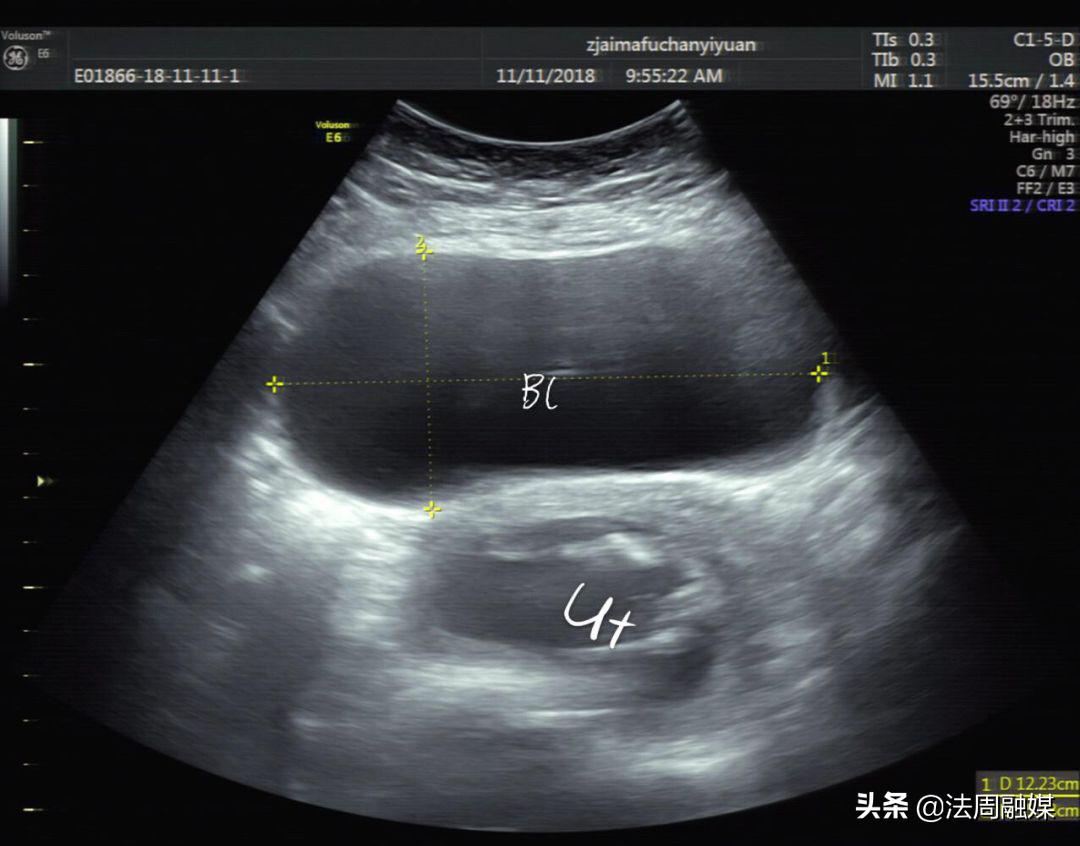

时间回到前一天。4月5日上午,何女士起床后发现自己排尿困难,并且下腹持续性胀痛,在丈夫的陪同下,夫妻俩来到常德市妇幼保健院就诊。孕产保健科主任杨御华见何女士左手按着下腹部且面色艰难,便优先接诊了何女士。经检查后怀疑是“尿潴留”,迅速开具了B超单并标明加急,第一时间为何女士安排了B超。经超声影像科童立里副主任医师B超检查:膀胱过度充盈,子宫明显后倾后屈位,宫内见胎儿回声,胎心胎动存在。确诊子宫箝闭症。

膀胱明显充盈表现细长,后方见妊娠子宫回声

子宫明显后倾后屈,宫颈细长

尿潴留缓解,子宫位置已转前位,宫颈远离尿道